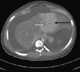

Pill ingestion